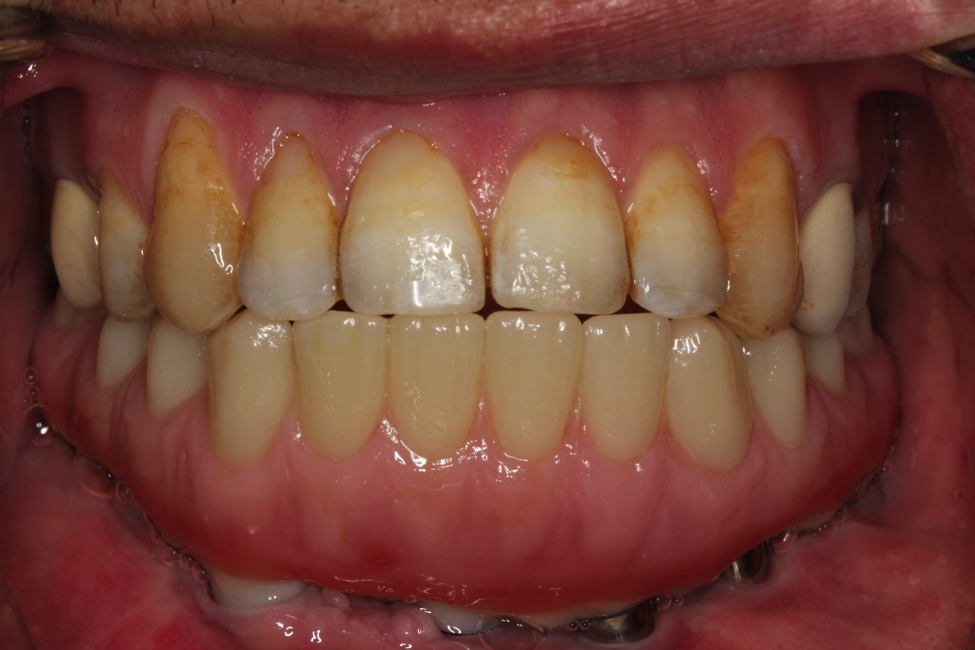

This patient has his entire jaw removed. He had part of his leg transplanted in his jaw and he came to us for implants and crowns. We placed implants in his jaw and made him fixed implant bridges. He traveled to us from Kuwait to have this done.